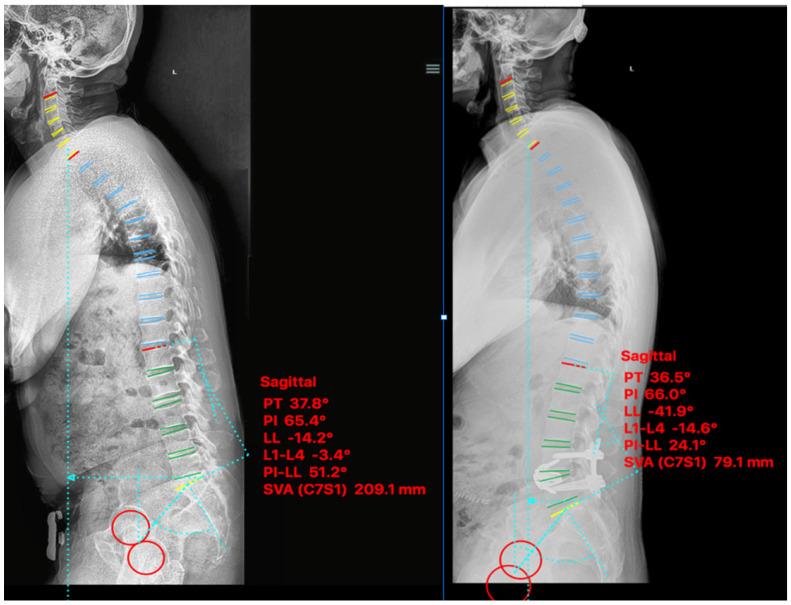

Loss of lumbar lordosis caused by single level degenerative spondylolisthesis can trigger significant sagittal plane imbalance and failure to correct lumbopelvic parameters during lumbar fusion can lead to poor outcome or worsening deformity. Anterior column release (ACR) through a pre-psoas approach allows the placement of a hyperlordotic cage (HLC) to improve lumbar lordosis, but it is unclear if the amount of cage lordosis affects radiological outcomes in real-life patient conditions. Three patients were treated with ACR and 30° expandable HLC for positive sagittal imbalance secondary to single-level spondylolisthesis. Patients reported baseline and post-operative Oswestry Disability Index (ODI) and Numeric Pain Score (NRS). Radiographic parameters of sagittal balance included lumbar lordosis (LL), sagittal vertical axis (SVA) and pelvic incidence-lumbar lordosis mismatch (PI-LL). Surgical indications were sagittal plane imbalance caused by L4-L5 degenerative spondylolisthesis (n = 2) and L3-L4 spondylolisthesis secondary to adjacent segmental degeneration (n = 1). Average post-operative length of stay was 3 days (range 2-4) and estimated blood loss was 266 mL (range 200-300). NRS and ODI improved in all patients. All experienced improvements in LL (x¯preop = 33°, x¯postop = 56°), SVA (x¯preop = 180 mm, x¯postop = 61 mm) and PI-LL (x¯preop = 26°, x¯postop = 5°). ACR with expandable HLC can restore sagittal plane balance associated with single-level spondylolisthesis. Failure to perform ACR with HLC placement during pre-psoas interbody fusion may result in under correction of lordosis and poorer outcome for these patients.

单节段退变性脊椎滑脱导致腰椎前凸丢失可引发明显矢状面失衡,如果在腰椎融合过程中不能纠正腰骨盆参数,可导致不良结果或畸形恶化。前路柱松解(ACR)经前路松解可使超前凸椎间融合器(HLC)的放置,从而改善腰椎前凸,但尚不清楚在现实患者情况下,椎间融合器的前凸角度是否会影响影像学结果。3 例单节段脊椎滑脱继发阳性矢状面失衡患者采用 ACR 和 30°可扩张 HLC 治疗。患者报告术前和术后 Oswestry 功能障碍指数(ODI)和数字疼痛评分(NRS)。矢状面平衡的影像学参数包括腰椎前凸(LL)、矢状垂直轴(SVA)和骨盆入射角-腰椎前凸不匹配(PI-LL)。手术指征为 L4-L5 退变性脊椎滑脱(n = 2)和 L3-L4 脊椎滑脱继发邻近节段退变(n = 1)导致的矢状面失衡。术后平均住院时间为 3 天(范围 2-4 天),估计失血量为 266 mL(范围 200-300 mL)。所有患者的 NRS 和 ODI 均改善。所有患者均改善了 LL(x¯术前=33°,x¯术后=56°)、SVA(x¯术前=180mm,x¯术后=61mm)和 PI-LL(x¯术前=26°,x¯术后=5°)。前路柱松解联合可扩张 HLC 可恢复与单节段脊椎滑脱相关的矢状面平衡。如果在前路融合过程中未能进行 ACR 和 HLC 放置,可能会导致前凸角度矫正不足,这些患者的结果较差。